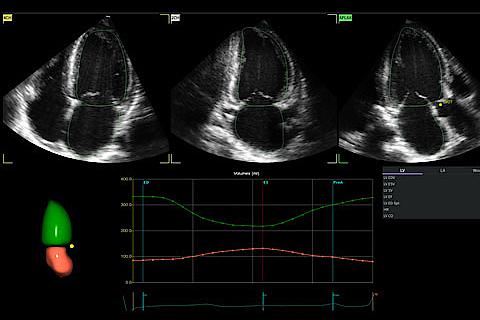

Clinical Images

Explore a new world of color and definition

4Vc-D A4C Multi-Slice

4D Volume with MPR